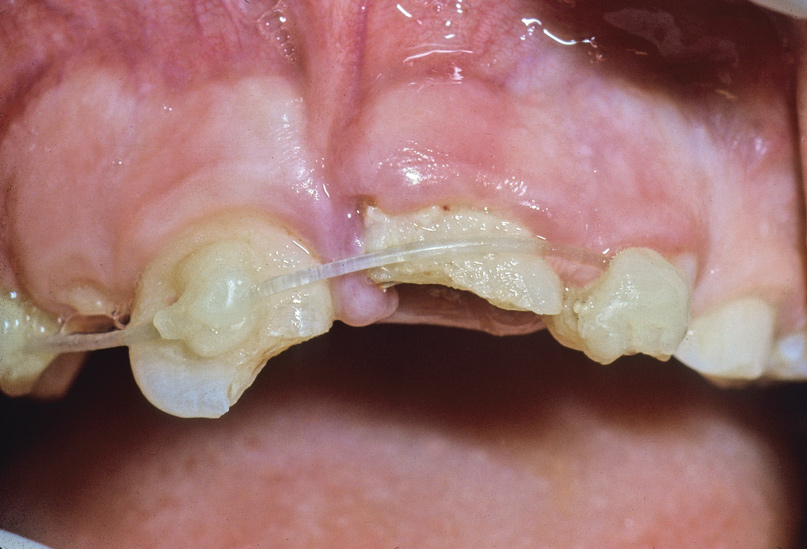

Two months after completion of the endodontic treatment of tooth No. 9, the patient presented with a chisel fracture about 2 mm apical to the cementoenamel junction (CEJ). The crown of tooth No. 9 was removed that day and Ca(OH)2 was replaced in tooth No. 8. Clinical photographs and radiographs were taken 3 months after removal of the coronal segment of No. 9 (Figure 3 and Figure 4). The missing crown of No. 9 was replaced with a temporary partial denture.

Fig 3. Age 10. Radiograph of teeth Nos. 8 and 9, 3 months after the fractured coronal segment of No. 9 was removed. Note the coronal level of the root relative to tooth No. 10.

Figure 3

Fig 4. Age 10. Occlusal view of maxillary ridge.

Figure 4